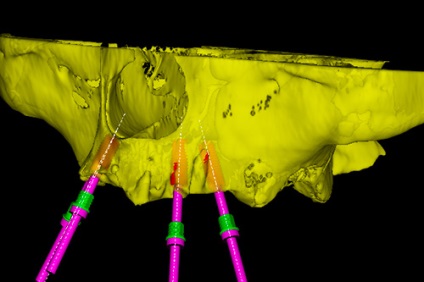

Mi egy felmérés az állkapocs szövet és a beteg test egészére, 3D modellezés jövőbeli virtuális fogak és a működés

2. 3D-modellezés a protézis és a műtét.

Ebben a szakaszban az orvos felméri, hogy milyen nehézségekkel szembe kell néznie. A modern technológia lehetővé teszi, hogy szimulálja a funkciók megelőző stádium jövő implantátumokat.

Az orvos termel implantáció felső és alsó állkapocs.